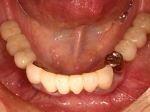

術後(鏡像)

術後口腔内(正面観)もう入れ歯は要らなくなりました。